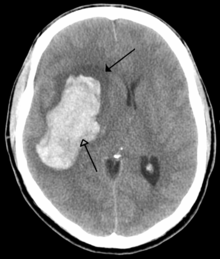

Haemorrhagic stroke is often also known as Intracerebral (Intracranial) haemorrhage. This happens when a blood vessel in the brain ruptures and blood flows into the brain tissue. In western population it accounts for 15 – 20 % of all strokes. In stark comparison in Indian population it accounts for about one third (32%) of all strokes. High blood pressure is the leading cause of bleeding in the brain. The higher prevalence of undiagnosed and uncontrolled blood pressure in the Indian population is thought to be the reason for the higher occurrence of bleeding in brain in this population group.

In comparison to Ischaemic stroke the brain tissue damaged by bleeding into the brain cannot be recovered. Despite this urgent and timely treatment is still extremely important in this kind of stroke. Urgent control of blood pressure within the first 6 hours and administration of clot stabilising drugs during a similar time period has shown to reduce the amount of bleeding in the brain and thus save lives and reduce disability.